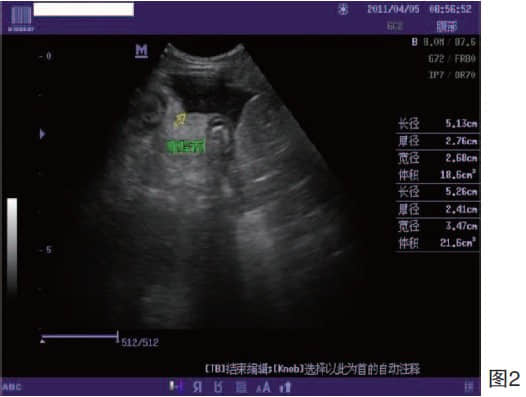

腊肠犬,公,11岁,体重6Kg,主人发现该犬呕吐,消瘦,没有食欲, 来我院就诊,X射线检查没有发现异常,血液指标也趋于正常。所以进行常规治疗,补液,消炎。治疗2天后,仍没有好转的迹象,又做一次血液化验(图1),白细胞异常增多,B超显示:腹腔整体回声明显增强,且有腹腔积液。(图2)所以,和主人沟通,建议开腹探查。